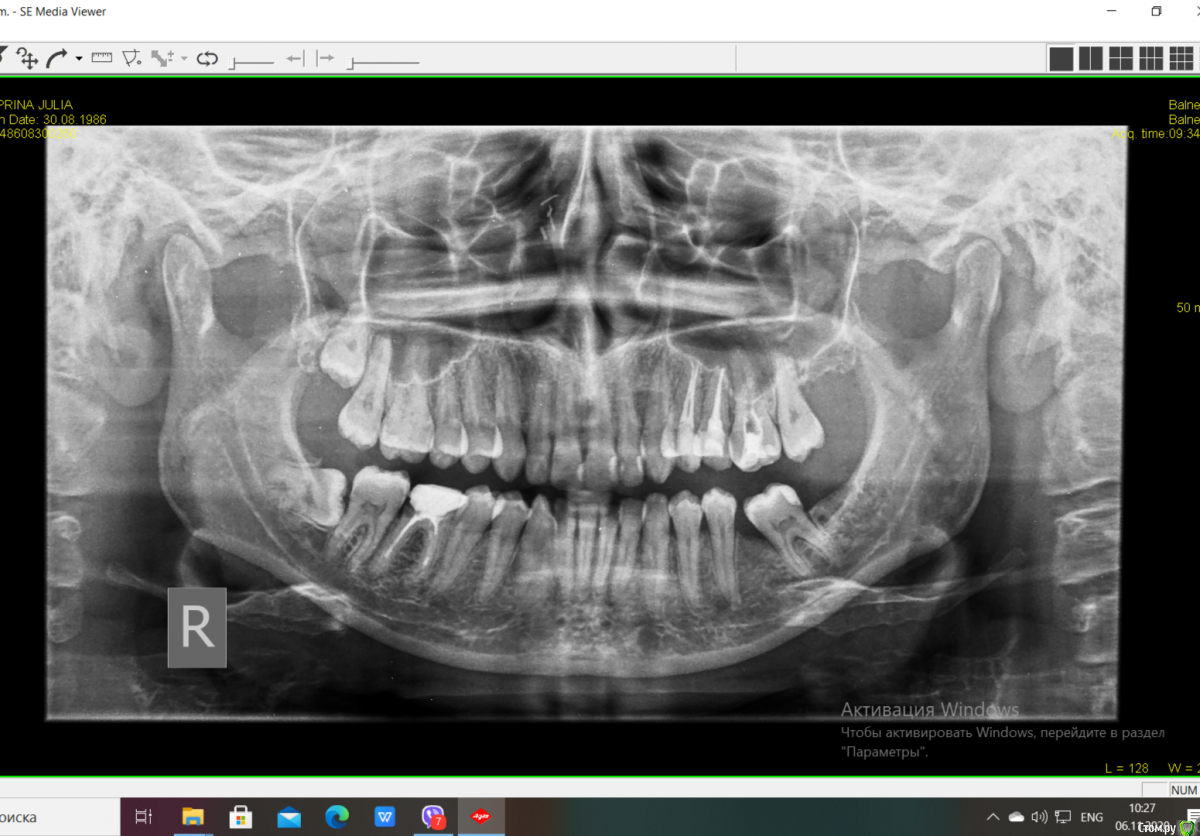

Алина08 Опубликовано 7 ноября, 2020 Поделиться Опубликовано 7 ноября, 2020 Добавлю ещё в эту тему. Здравствуйте, дорогие доктора, помогите пожалуйста,прилагаю панорам снимок. Слева были в феврале удалены мудрости, сверху вырезано,снизу вырван.Удаления были не сложные, но постоянно что-то мешало мне в ухе, а сейчас так вобще больно нажимать на челюсть снизу, болит челюсть, где 7 зуб и до подбородка. На кт было очень похоже на остаток корня рядом с корнем 7 зуба , но потом сказали это цвет кости такой другой. Сделала панораму и по мне так снизу явно видно, что там что-то есть. Как думаете? И что сверху слева у корня 7 зуба рядом?Мучают и боли лица, область пазухи и до глаза, там зубы 4 перелечили, 5 вывели материал сильно за корень , перелечили мта. Сейчас с 6 зуба достают пломбировочный материал, имеется аллергия на никель, в гутаперчи есть оксид никеля.Всё под микроскопом делалось, претензий к зубам нет у врачей, а боли начались как вскрыли 5 зуб, потом перелечили 4,не прошло, было ощущение распирания зубов, вскрыли 6 там дентикль, теперь его перелечивают, исключая аллерген контакт со слизистой, имею большие пазухи . Боль постоянная, распирающая, чувство давления на зубы. Может ли это боль снизу идти наверх? Выпито куча таблеток от невралгии, не помогает. Предлагают рвк 5 зуба, так как он на стук и кушать самый больной, у 6 зуба, если материал весь не достанут, осталось пару мм, тоже один корень верхушку убрать, но там пазуха рядом, не факт, что врач возмется. Придагалаю панораму и маленькие снимки 4,5,6 зубов.Больше меня сейчас волнует, есть ли кусок корня снизу от 8 зуба. Ссылка на комментарий

Алина08 Опубликовано 7 ноября, 2020 Автор Поделиться Опубликовано 7 ноября, 2020 (изменено) Ещё прилагаю панорамы после удаления мудростей слева. Посмотрите пожалуйста. Изменено 7 ноября, 2020 пользователем Алина08 Ссылка на комментарий